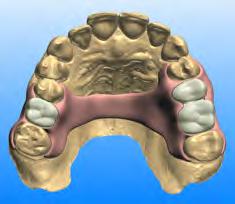

12. Ludwig DC, Dodson TB, Morrison SD. U.S. oral and maxillofacial residents’ experience with transgender people and perceptions of gender-affirmation education: a national survey. J Dent Educ 2019 Jan;83(1):103-111.

Laura Rhein, D.D.S., is a former resident, Jamaica Hospital Medical Center, New York, NY. She practices general dentistry in New York City and Connecticut.

Michael J. Mand, D.D.S., is an attending dentist in the General Practice Residency Program in the Department of Dental Medicine at Jamaica Hospital Medical Center, New York, NY, and practices general dentistry in Brooklyn, NY.

Benjamin Solomowitz, D.M.D., is director, General Practice Residency Program, Department Dental Medicine, Jamaica Hospital Medical Center, New York, NY, and a dentist anesthesiologist.

The New York State Dental Journal ● APRIL 2023 21

Dr. MandDr. Solomowitz Dr. Rhein

Oral Health Considerations for Aging Patients Living with HIV/AIDS

ABSTRACT

People living with HIV/AIDS (PLWH) have an increased life expectancy due to advances in antiretroviral therapy. In 1996, the life expectancy for a 20-year-old living with HIV was 39 years. Today, it is >70 years. As life expectancy increases, PLWH are burdened with age-associated comorbidities. This paper reviews the interaction between aging and HIV and how it affects social, physical and oral health issues. The shift in demographics presents new challenges for clinicians in how to identify, address and manage these complex manifestations. This review summarizes how to approach HIV-related changes when providing care as a dental clinician.

Advances in antiretroviral therapies are allowing people living with HIV/AIDs (PLWH) to live longer than ever before.[1] Early initiation and increased effectiveness of antiretroviral therapy have increased the life expectancy of PLWH to nearly that of the general population.[2] In 2018, the majority of people in the United States with an HIV diagnosis were over 50 years old.[3] Given increased life expectancy and incident HIV infections in

older adults, it is estimated that over 70% of PLWH will be over 50 years old by 2030.[4]

Antiretroviral therapy is recommended for all PLWH, but it is especially important for older PLWH, because they are more likely to present with comorbidities and a weakened immunologic response to treatment.[1] Current combined antiretroviral therapy (cART) for PLWH typically includes two nucleoside reverse transcriptase inhibitors with a third drug: an integrase strand transfer inhibitor; a nonnucleoside reverse transcriptase inhibitor; or a protease inhibitor with a pharmacokinetic enhancer.[1] The most recent data also support the use of a two-drug regimen: dolutegravir and lamivudine.[1] The most common cause of treatment failure is poor adherence to cART, so clinicians should identify factors, such as neurocognitive deficits or hormonal changes, that might cause older patients to miss doses.[1]

As the rates of morbidity and mortality decline, the prevalence of older PLWH increases, presenting a shift in demographics and a new set of challenges clinicians must face. The complex interaction between aging and HIV presents unique challenges for older PLWH, including social, physical and oral health-related issues. Dentists can play an important role in identifying these issues in older patients living with HIV, referring for appropriate care and services and mitigating oral symptoms and discomfort.

Social Issues Affecting Older PLWH

Oral health–related quality of life (OHRQoL), as measured by the well-validated and frequently used Oral Health Impact Profile, is

older aids patients

22 APRIL 2023 The New York State Dental Journal

Madeleine Daily, D.D.S.; Susan Liu, D.D.S.; Yuna Park, D.D.S., M.P.H., M.S.; Emily Byington, M.S.W.; Ivette Estrada, M.A., M.Phil.; Sunil Wadhwa, D.D.S.; Carol Kunzel, Ph.D.

a measure of the perceived effect of oral health on physical and social functioning and self-image.[5] There is strong evidence indicating OHRQoL is most negatively affected by dental caries and periodontitis.[6] Older age, unmet dental needs, smoking, loneliness and depression are also associated with worse OHRQoL.[5] For PLWH, health-related quality of life is most negatively affected physically, followed by psychologically.[6]

Studies have shown that PLWH experience unmet dental needs twice as frequently as unmet medical needs, a problem exacerbated for patients without dental insurance.[10] PLWH who have been exposed to long-term antiretroviral therapy are more likely to experience medication-induced xerostomia, which leads to dental caries, as well as halitosis, candidiasis and gingivitis.[6] Recent data demonstrate that, in addition to decayed teeth, prosthodontics treatment needs and drug use have the most significant negative impact on OHRQoL for PLWH.[7]

nutrition, there should be an increased emphasis on early preventive dental care for older PLWH, such as reducing levels of plaque.[9]

Depression and loneliness are major issues for older patients living with HIV. Patients with depression have worse oral health indicators, such as DMFT index (the sum of the number of decayed, missing due to caries, and filled teeth in the permanent teeth) and mean missing teeth, and lower OHRQoL, even after controlling for age and comorbidities.[8] Older PLWH experience an estimated 39% to 58% higher rate of loneliness, which correlates with an increased likelihood of using cigarettes, alcohol or other substances.[4]